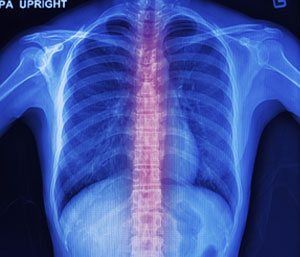

Yes. All reputable chiropractors should perform an initial examination including X-rays, if necessary, to first determine if the patient is a chiropractic candidate or not.

Once the determination is made that a subluxation exists in the spine, then, chiropractic adjustments are the only treatment course available. Chiropractic adjustments are very safe, especially when utilizing low-force technology, such as Activator and Sigma Instrument techology techniques.